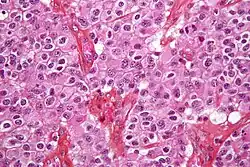

Pathology

Maximal safe surgical resection (to preserve as much neurological function as possible) and histologic examination of the tumor is also required to aid in the diagnosis.[24] Cancer cells may have specific characteristics.

Atypia: an indication of abnormality of a cell (which may be indicative of malignancy). Significance of the abnormality is highly dependent on context.[53]

Neoplasia: the (uncontrolled) division of cells that is characteristic of cancer.[54]

Necrosis: the (premature) death of cells, caused by external factors such as infection, toxin or trauma. Necrotic cells send the wrong chemical signals which prevent phagocytes from disposing of the dead cells, leading to a buildup of dead tissue, cell debris and toxins at or near the site of the necrotic cells[55]

Local hypoxia, or the deprivation of adequate oxygen supply to certain areas of the brain, including within the tumor, as the tumor grows and recruits local blood vessels.[56]

By behavior

Brain tumors can be cancerous (malignant) or non-cancerous (benign). However, the definitions of malignant or benign neoplasms differ from those commonly used in other types of cancerous or non-cancerous neoplasms in the body. In cancers elsewhere in the body, three malignant properties differentiate benign tumors from malignant forms of cancer: benign tumors are self-limited and do not invade or metastasize. Characteristics of malignant tumors include:[63]

- uncontrolled mitosis (growth by division beyond the normal limits)

- anaplasia: the cells in the neoplasm have an obviously different form (in size and shape). Anaplastic cells display marked pleomorphism. The cell nuclei are characteristically extremely hyperchromatic (darkly stained) and enlarged; the nucleus might have the same size as the cytoplasm of the cell (nuclear-cytoplasmic ratio may approach 1:1, instead of the normal 1:4 or 1:6 ratio). Giant cells – considerably larger than their neighbors – may form and possess either one enormous nucleus or several nuclei (syncytia). Anaplastic nuclei are variable and bizarre in size and shape.